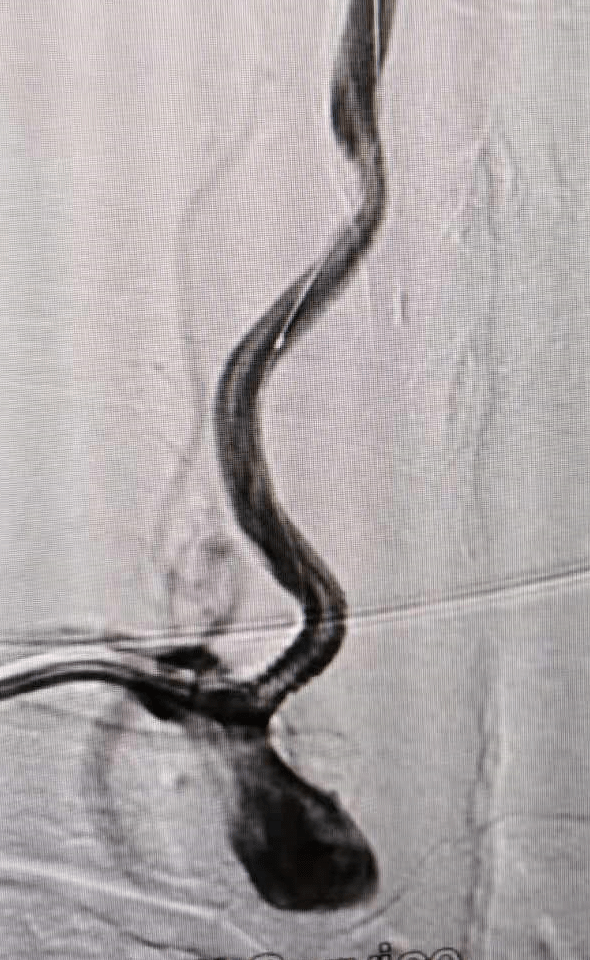

患者曹某,男,60岁。因言语笨拙伴右侧肢体活动不灵3天入院。入院诊断为:脑梗死。7月1日经桡动脉脑血管造影显示:左颈内动脉闭塞、左椎动脉闭塞、右椎动脉开口部位重度狭窄。考虑到患者双侧椎动脉一侧闭塞,一侧严重狭窄,打开狭窄一侧血管对改善后路供血意义重大。向患者及家属交代病情后,其同意我们的治疗方案,对我们的技术充满信心。其后我们认真测量狭窄部位各项指标,选择合适的球扩支架,经桡动脉入路为我们提供了最直接、稳定的手术路径,顺利的到达狭窄部位后释放支架。造影见狭窄明显改善,手术在半小时内获得成功。

术前椎动脉开口狭窄(图)